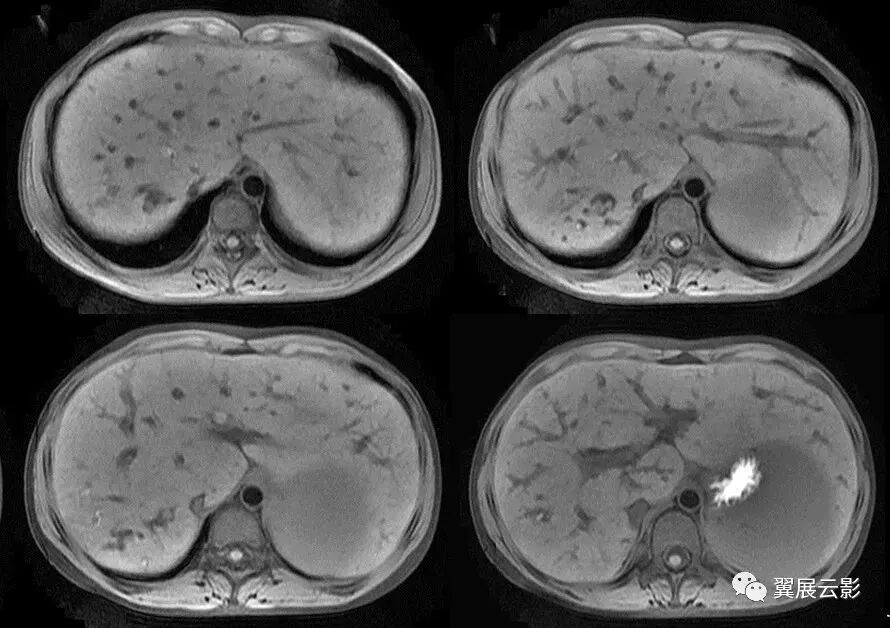

19、靶征

有多个名称,分别是:环靶征;双靶征;环征;双环征;三环征等。肝脓肿CT增强扫描的典型表现,因呈靶环状而得名。表现为肝内囊样低密度肿块病灶,边缘多数较模糊,脓肿周围往往出现不同密度的环形带(环征或靶征),增强扫描脓肿壁呈不同程度的环状强化,脓肿壁可为单环、双环或二环。

靶征是肝脓肿的典型征象,是脓肿形成期的表现。此期脓腔液化坏死彻底,脓肿壁可为单环,双环或三环,单环代表了脓肿壁,其周围水肿不明显;双环的内环代表脓肿壁,外环代表周围水肿带;三环表明脓肿壁由三层构成,外层(中环)为纤维肉芽组织,强化最明显,内层(内环)由炎性组织构成,强化不如外层纤维肉芽组织。肝脓肿靶征的出现代表着一定阶段病变的病理过程,为肝脓肿的特征性表现,对诊断很有价值。

大多数学者把肝脓肿的脓肿形成期CT表现认为是典型表现,表现为肝内囊样低密度肿块,病灶边缘多数较模糊,脓肿周围往往出现不同密度的环形带(环征或靶征),增强扫描脓肿壁呈不同程度的环状强化;少数患脓肿内出现气体,此时可肯定诊断。

增强扫描使病灶内部结构、病灶边缘与正常肝组织的关系显示得更清楚。门脉期可显示肝脓肿较典型的CT征象,为典型三层病理改变增强后的CT表现,中心坏死区无强化,中间层为介于液化坏死区与正常肝组织之间的低密度带晕带环,外围层与正常组织分界模糊。慢性期由于脓肿周围形成血管丰富的结缔组织包膜,脓肿壁显著环形强化,其密度高于肝组织。环绕脓腔的为强化环,可以是单环、双环甚至三环。3个环相当于脓壁的3种病理结构:水肿、纤维肉芽组织和炎性坏死组织。如果3种结构存在则出现三环,否则出现双环或单环。

双环征

三环征